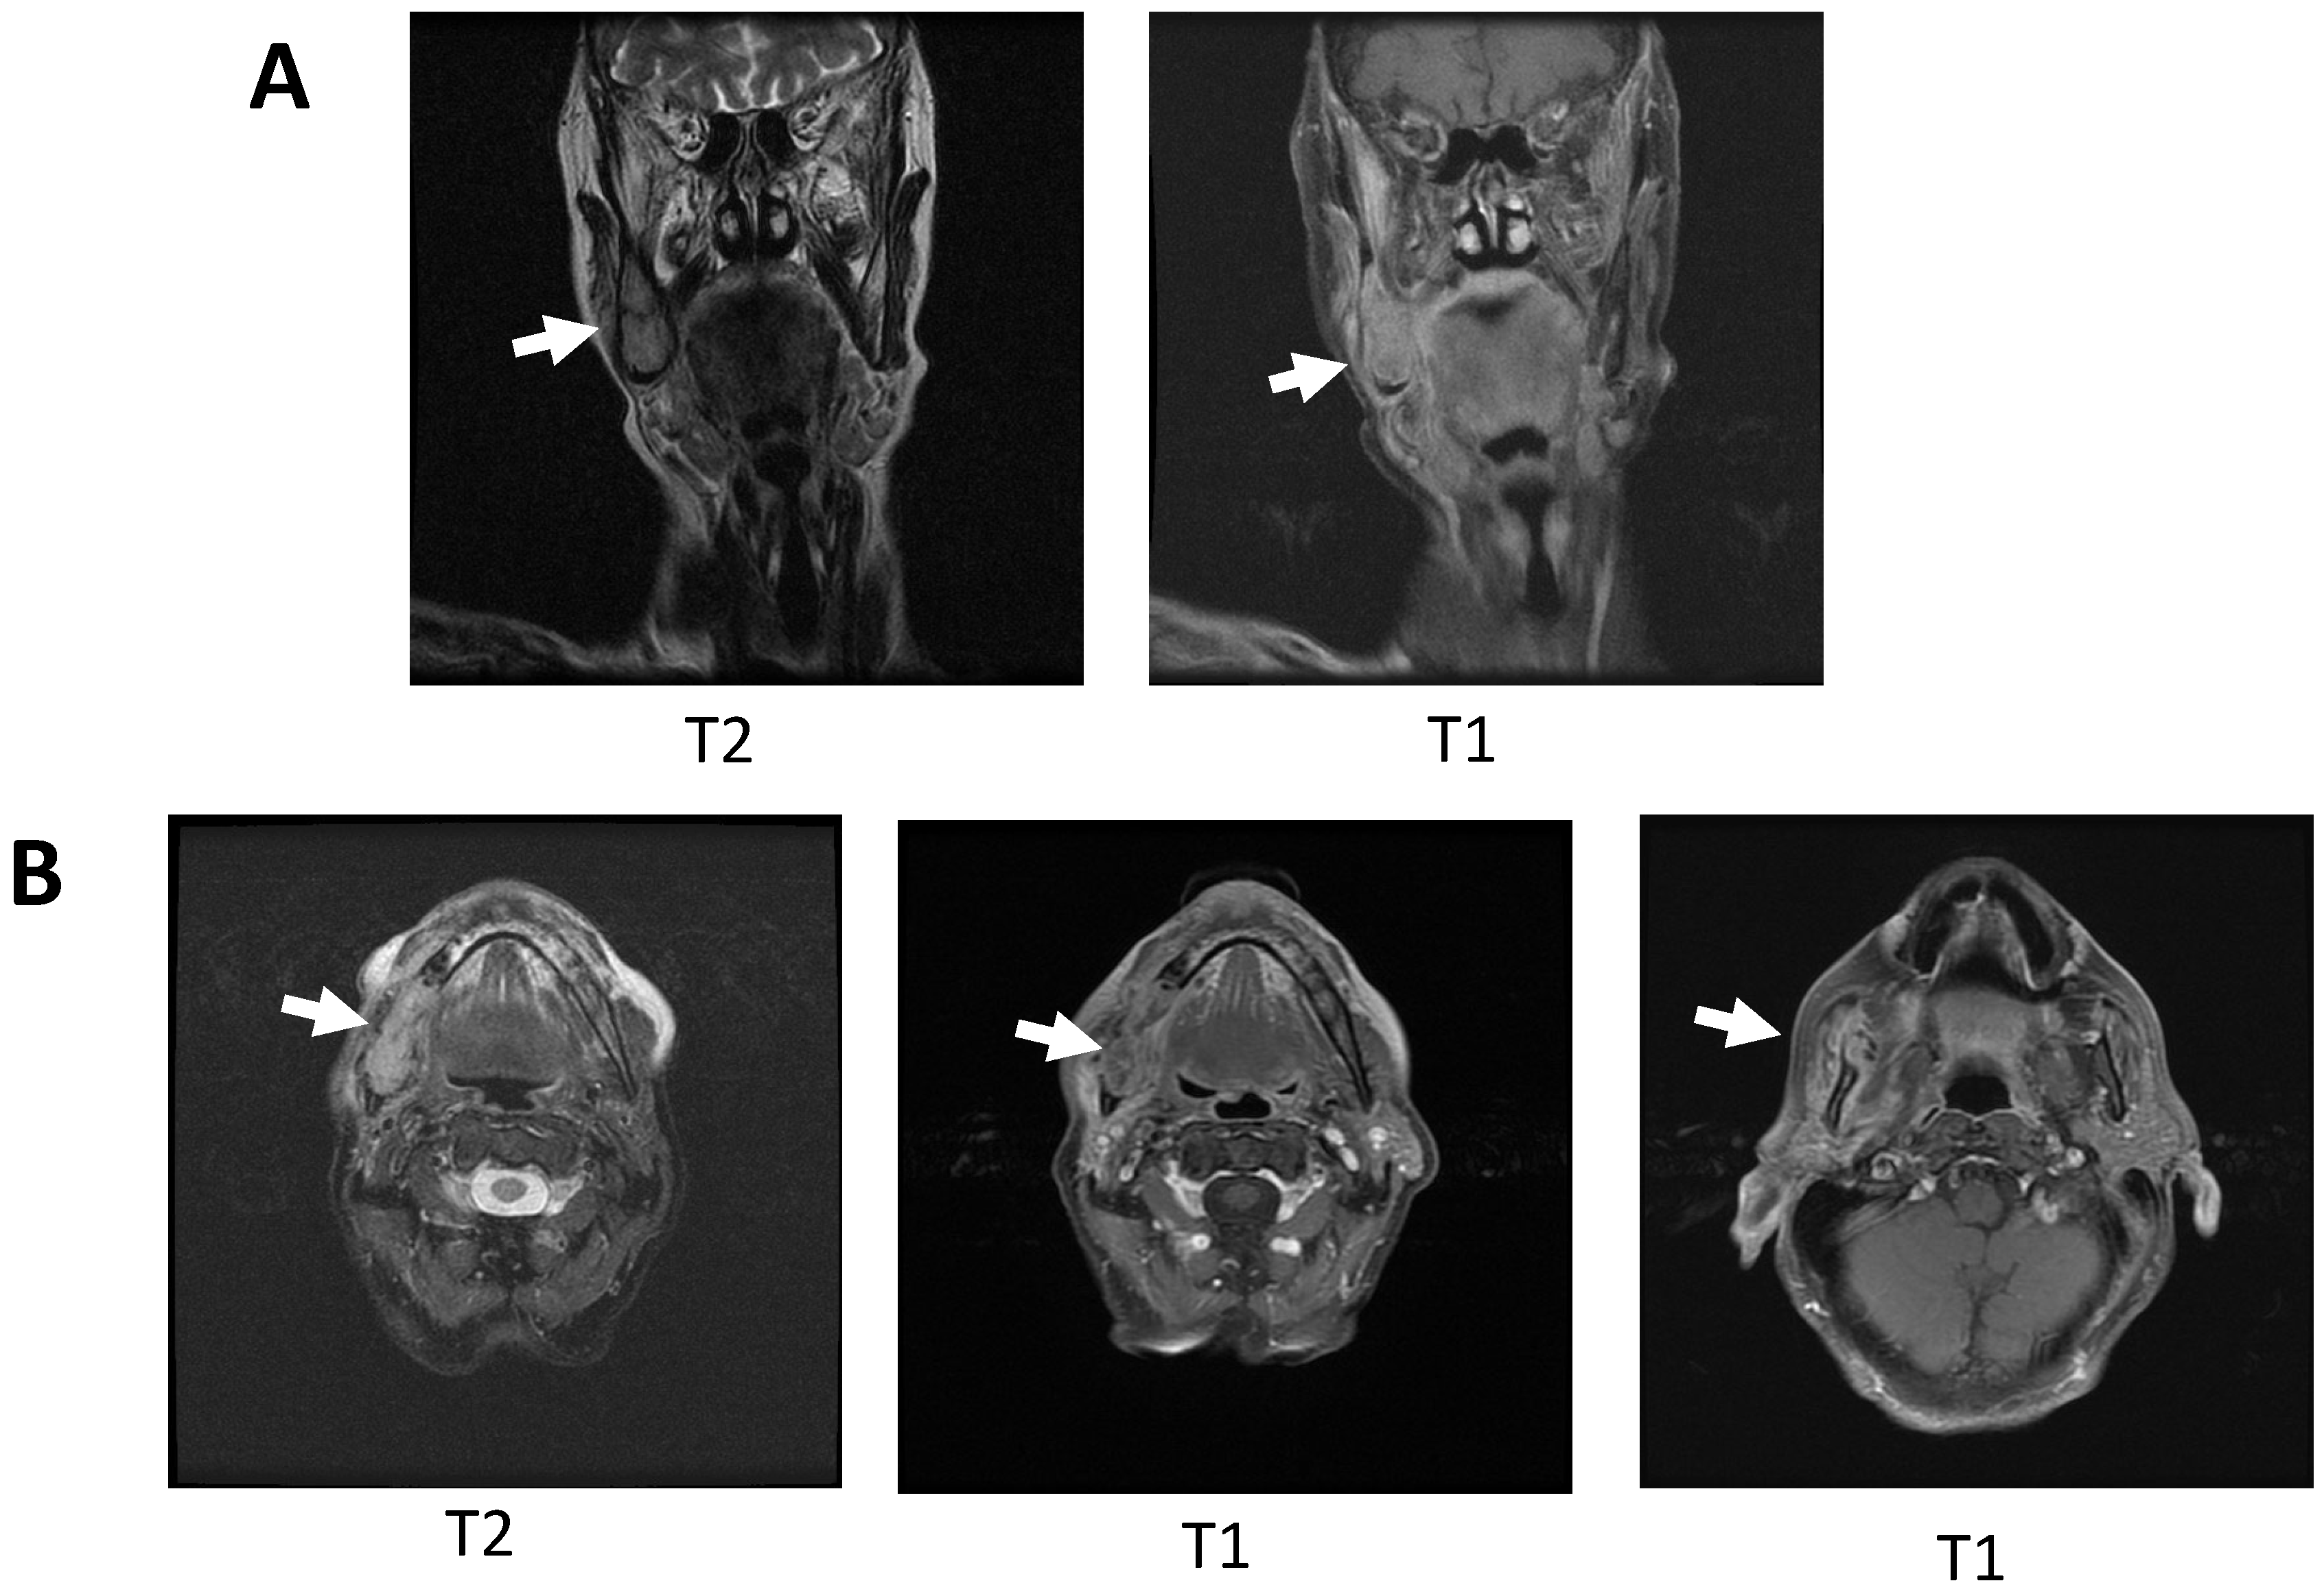

2.1. Clinical and Histological Manifestations of the Tumors

4.2. Magnetic Resonance Imaging